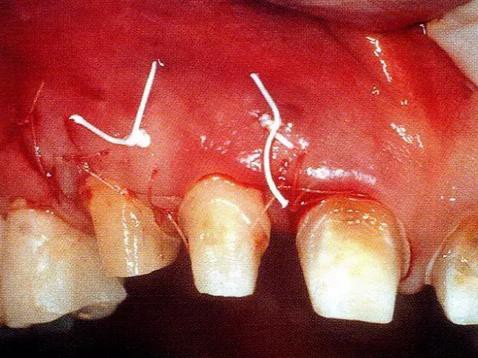

▼圖13-5 通過垂直褥式縫合法進(jìn)行緊密的縫合。